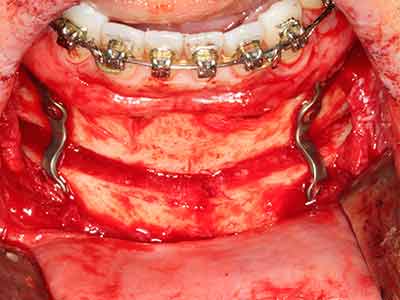

Piezo surgery has additional advantages when harvesting bone blocks. In addition to the high precision with osteotomy described above, the use of the thin saw tips specifically minimizes loss of material. Greater loss of material during harvesting can be expected with the thicker instrument tips, particularly when using Lindemann drills (Lakshmiganthan, Gokulanathan et al. 2012). The basal separation, which is necessary particularly for retromolar block transplants, is simplified by specially designed rectangular saws, with the result that piezo surgery is viewed as a precise, simple and safe procedure for harvesting retromolar bone blocks (Happe 2007) (Fig. 1-12).

Indication: Bone splitting

Bone tissue is not simply a mineral structure but also contains a substantial proportion of collagen fibres. This means it not only has good compressive strength but also a degree of flexibility, which can be taken advantage of when performing bone augmentations. In the classical expansion procedure using bone splitting, the atrophied alveolar ridge is split longitudinally and carefully expanded after reaching an adequate osteotomy depth (Fig. 13-16), ideally without substantial removal of the periosteum (Brugnami, Caiazzo et al. 2014, Stricker, Fleiner et al. 2014). Screw and plate systems with increasing expansion distance have proven effective in separating the two bone lamellae while remaining below the fracture threshold. In general, residual bone widths of at least 3–4 mm are required (Chiapasco, Zaniboni et al. 2006) to guarantee adequate flexibility and sufficient bone coverage of the future implants. If necessary, a vertical relief osteotomy on one or both sides can improve flexibility. A combination with additional augmentation techniques, particularly on the buccal side, has been described as an alternative to the classical technique.

The splitting procedure is particularly atraumatic and there is no significant loss of dimension when using piezosaws, and there are no significant differences between implants in split jaws and implants in an alveolar ridge without a bone deficit (Chiapasco, Zaniboni et al. 2006, Danza, Guidi et al. 2009). However, sufficient continuous irrigation is essential, particularly with locally restricted and deep splitting to prevent thermal stress in the apical osteotomy regions.